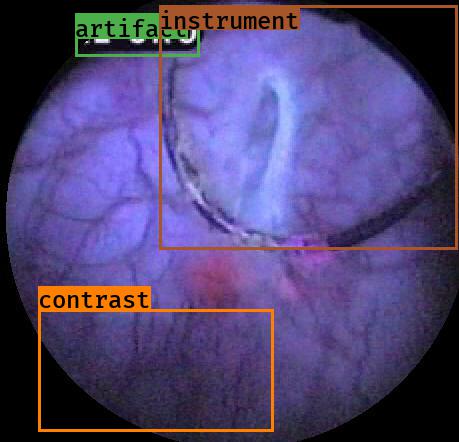

Examples for bounding box annotations for detection are shown in Fig. 2. It can be observed that while multiple boxes are annotated for several small specular areas; contrast, blur and instrument have relatively larger areas. Due to the overlap between two or more classes, the annotation by experts varied. This was minimized by following the detailed annotation protocol above. For semantic segmentation, a larger area mask was preferentially used to delineate locally very cluttered small specularity artifacts (see Fig. 3).